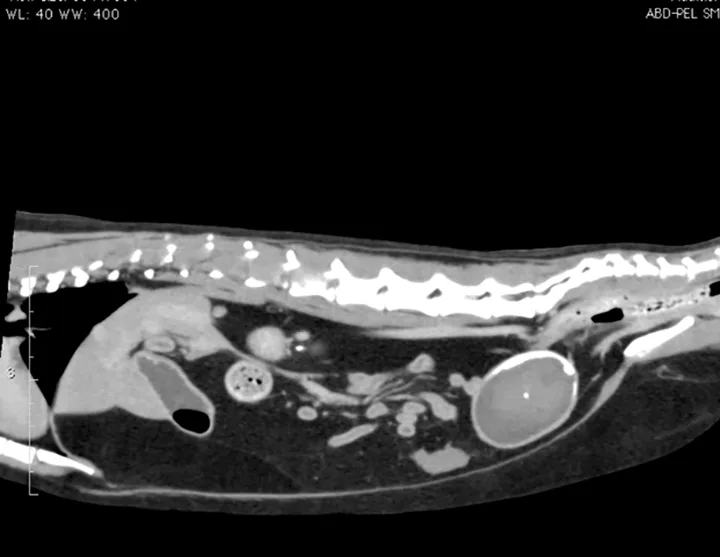

Additional diagnostic tests included abdominal ultrasound (Figure 2) and computed tomography (CT) scan with IV contrast media (Figure 3).

Figure 3. There is a filling defect taking up the majority of the lumen of the urinary bladder as evidenced by only a thin strip of positive contrast medium present in the periphery of the urinary bladder.

1. Urinary bladder hematoma admixed with sandy calculi was suspected. The structure had no blood flow, which made a neoplastic process less likely. Given the findings of the previous abdominal FAST scan, a urinary bladder hematoma was the top differential.

2. The choice was made to surgically remove the urinary bladder hematoma via cystotomy. The source of the blood was thought to be renal because of the size and severity of the clot. Ivan was likely continuing to bleed into his urinary tract over the course of his stay because he continued to exhibit hematuria and his PCV continued to drop. This suggested that a moderate-sized bladder after the perineal urethrostomy was actually an organized blood clot, not urine, because there is minimal bleeding from the urinary tract after a perineal urethrostomy. Another option would have been to try to dissolve the clot with tissue plasminogen activator, as is done in humans6; however, given the size of the clot, surgery was decided to be the better option.